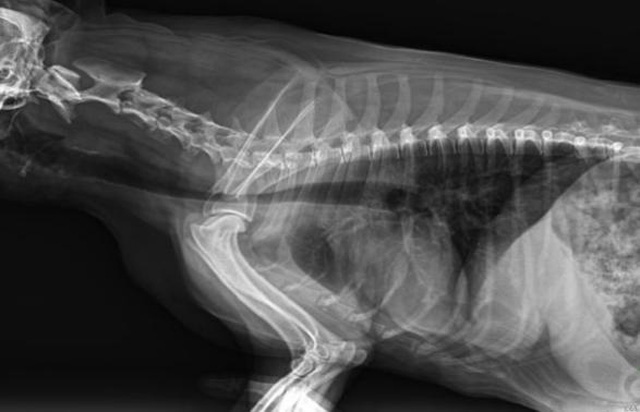

從臨床角度出發(fā),大力發(fā)展動(dòng)態(tài)DR,以精準(zhǔn)的診斷為小動(dòng)物保駕護(hù)航。寵物DR升級(jí)使用雙焦點(diǎn)球管,大尺寸平板探測(cè)器,超高頻逆變高壓發(fā)生器。醫(yī)用纖維板臺(tái)面,防止寵物劃傷。寵物DR整機(jī)小巧實(shí)用,骨略結(jié)構(gòu)和器官位置,分類詳細(xì),運(yùn)算更快,讓拍攝條件更科學(xué),有助于提高診斷的準(zhǔn)確性和效率。安裝移動(dòng)非常方便。低輸入電流設(shè)計(jì),220伏常規(guī)電壓。多品種動(dòng)物程序設(shè)定,滿足各個(gè)臨床需求。成像效果顯著,寵物不能言語表達(dá),導(dǎo)致誤診率居高不下。寵物診療均以經(jīng)驗(yàn)診斷為主的方式,確保最小化輻射降低對(duì)醫(yī)生及動(dòng)物的影響。以滿足精細(xì)化的寵物醫(yī)療需求,成為診斷寵物內(nèi)外科疾病的必備工具。使醫(yī)院更有競(jìng)爭(zhēng)力,為醫(yī)院創(chuàng)收增光添彩。

寵物DR的操作流程是什么呢?第一步首先插上整機(jī)電源,然后按下主機(jī)電源。打開高壓發(fā)生器的電源,工作站主機(jī)電源。等待主機(jī)軟件的自動(dòng)啟動(dòng)。通過軟件登記檢查的寵物信息,選擇寵物檢查拍攝部位。調(diào)節(jié)限速器拍攝區(qū)域。關(guān)閉鉛房門,點(diǎn)擊開始拍攝按鈕。拍攝完成調(diào)整圖像并且輸出。